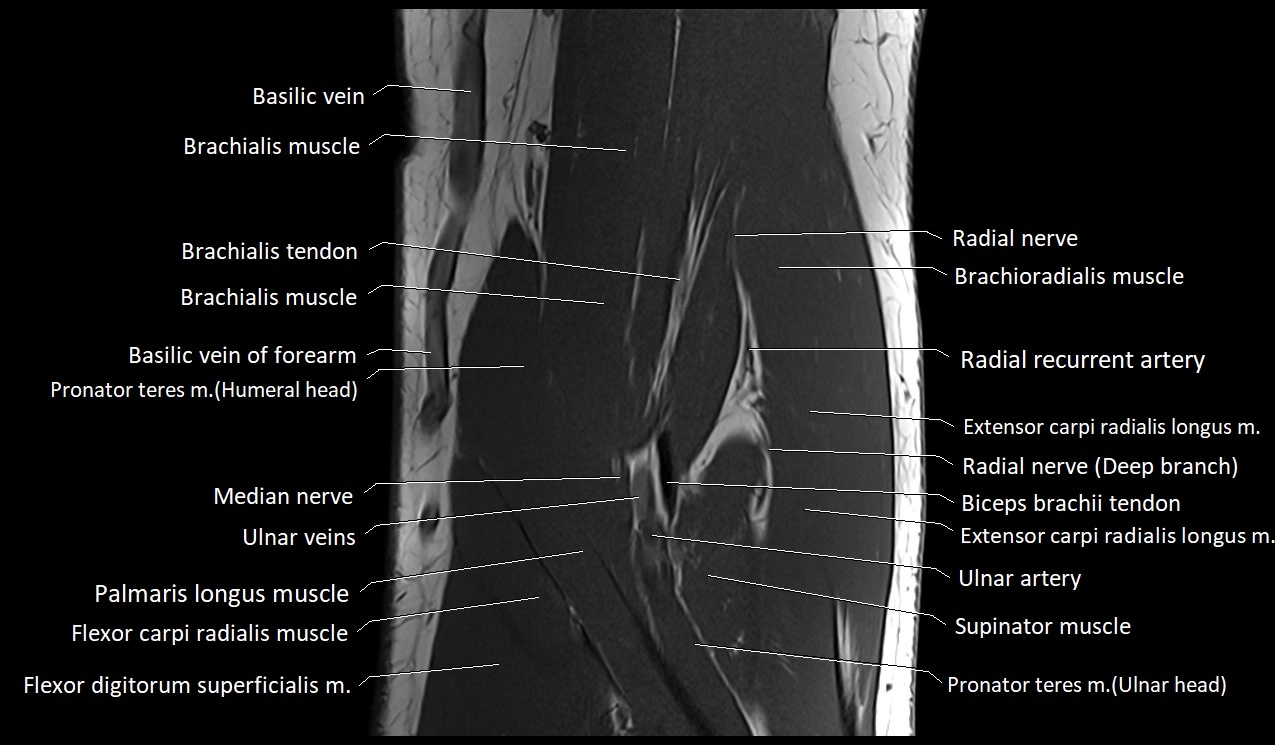

MRI image

image